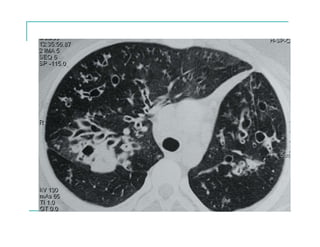

EVOLUCIÓN RADIOLÓGICA

Gérmenes más frecuentes

S.aureus: primeros años de vida

H.influenzae: puede producir colonización crónica

P.aeruginosa: infección pulmonar crónica más severa

que se asocia a un continuo y progresivo deterioro de la

función pulmonar.